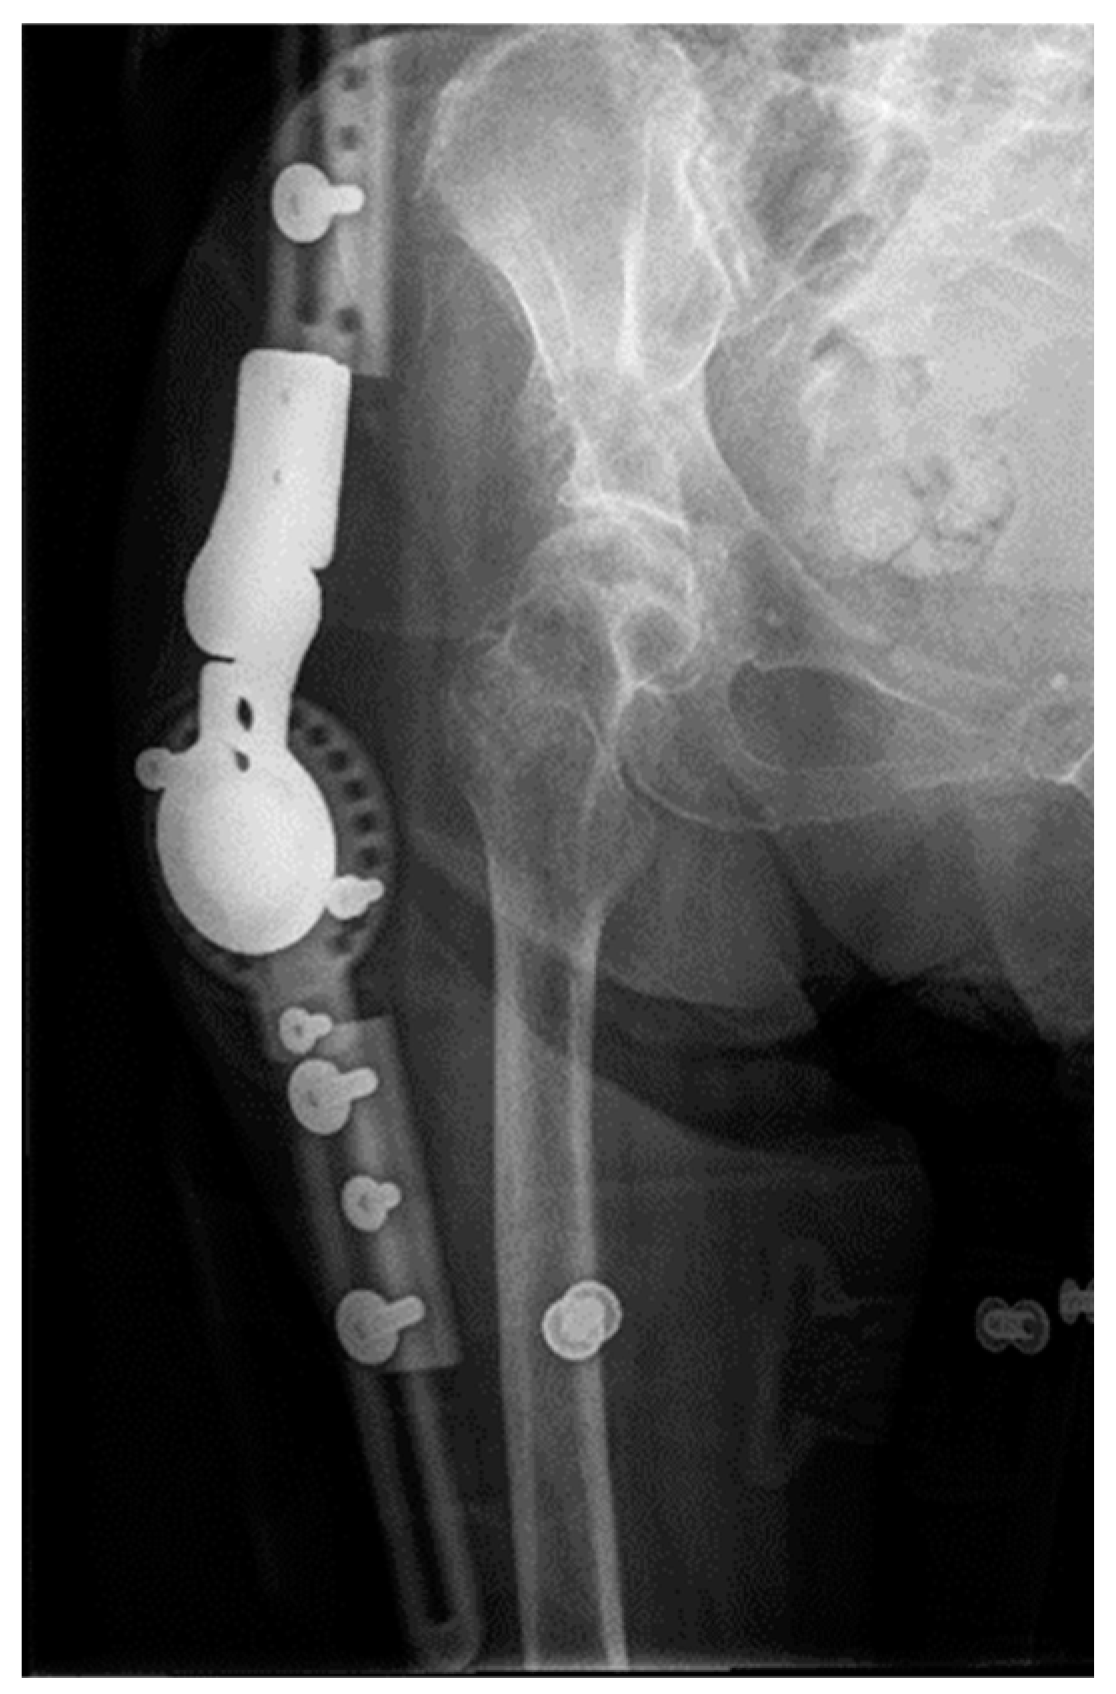

2.1. Two-Stage Open Reduction

2.2. Complications after Treatment